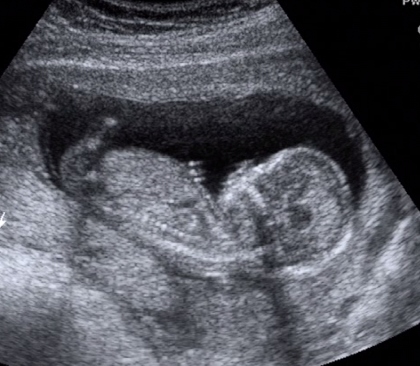

Mi megjöttünk az uh-ról! :D Uram sajna nem ért oda :(, de mi mamával áhitattal néztük Manó Gyereket fél órán keresztül! :D

Hála az égnek, minden rendben van, mindene megvan és működik is, minden tökéletes méretű rajta! Kóros elváltozás sehol nem látható! (A dvd-t most fogjuk megnézni büszke apájával... :wink: )

...Uram gazdagabb lett 10 Ft-tal... :oops: :cry: :twisted: :P

KISFIÚ!!! Ennyit a megérzésemről... :? :cry: :wink: :lol: Üdv a pocakomban Dániel Áron! :D